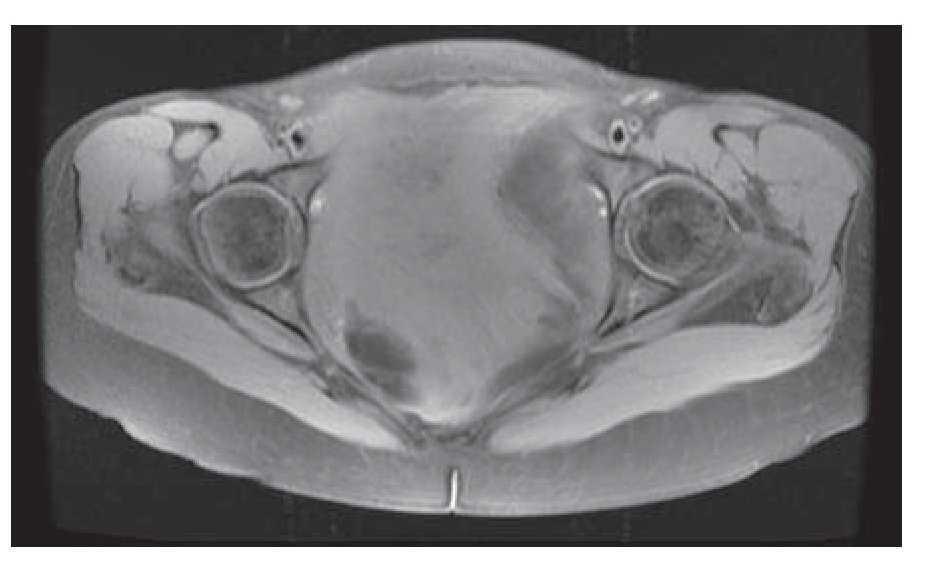

Mujer de 41 años de edad, sin antecedentes, que consultó por historia de dolor pélvico difuso, de baja intensidad, no irradiado, de ocho meses de evolución. Al examen físico se encontró una masa adherida a planos profundos y poco dolorosa a la palpación. Se le realizó una tomografía computadorizada que informó una extensa neoplasia pélvica de características malignas, que se extendía hasta el espacio isquiorectal, con desplazamiento y compresión de la vejiga y el útero, además de escaso líquido alrededor de la lesión (Figura 1). Se realizó una resonancia magnética nuclear que demostró una lesión de 14 x 14 cm, posiblemente de origen lipomatoso con degeneración mixoideangiolipomatosa, con probable infiltración al recto y sigmoides, dilatación pielo-ureteral bilateral por obstrucción del tercio distal de los uréteres (Figuras 2 y 3). Se realizó una colonoscopia que sólo evidenció desplazamiento del sigmoides por compresión extrínseca. Se le realizó una laparotomía exploratoria encontrando una masa pélvica de 15 x 20 cm, la cual se pudo separar de las estructuras adyacentes y resecar en su totalidad. El reporte histopatológico fue de una masa de 15 x 18 cm, con un peso de 260 g, de color amarillo-gris liso y opaco, de aspecto nodular y consistencia blanda. Al corte se encontraron áreas quísticas compatibles con angiomixoma (Figura 4). La paciente presentó una evolución satisfactoria, se le dio egreso. Actualmente se encuentra asintomática y sin datos de recurrencia.

Figura 1. Tomografía computadorizada que mostró masa de características malignas, desplazando y comprimiendo la vejiga y útero